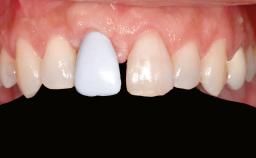

Ridge Preservation and Implant Placement for a Fixed Dental Prosthesis After a Car Accident

It is well known to clinicians that any removal of teeth will, over time, cause the dimensions of the alveolar ridge to be reduced by resorption of the bundle bone and by changes related to external modeling. This development is particularly evident in the crestal region with its thin buccal bone that consists of bundle bone almost entirely. The facial bone will rapidly resorb as blood supply from the periodontal ligament gets disrupted (Araújo and Lindhe 2005). There is no reason why traumatic tooth loss should not have the same consequences. It takes more than achieving implant osseointegration for a treatment outcome to be considered successful. No deficiency of bone or soft tissue is acceptable when an ideal esthetic outcome is the goal. Several articles (Sanz and coworkers 2011; Vignoletti and coworkers 2011) have reported on techniques of improving the alveolar ridge for implant treatment, notably focusing on protecting tissues from resorption.

Patient's Esthetic Expectations Low Medium High

Lip Line No exposure of papillae Exposure of papillae Full exposure of mucosa margin

Esthetic Risk High